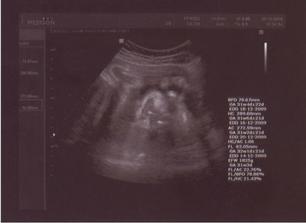

23.11.09 - velký UTZ + poradna - holčička váží cca 2845g, čípek v poho, CS 1, musím více odpočívat

4.12.09 - poradna + UTZ - holčička váží cca 3400g, čípek v poho, hrdlo zavřeno

11.12.09 - poradna + UTZ - holčička váží cca 3500g, čípek v poho, hrdlo zavřeno, streptokok negativní

18.12.09 - poradna + UTZ - holčička váží cca 3600g, jsem otevřená na 1 prst

22.12.09 - poradna + UTZ - holčička váží cca 3700g, čípek měkne a zkracuje se, otevřená jsem na 1 prst

29.12.09 - monitor + poradna + UTZ - holčička váží cca 3800g, jsem otevřená na 1 prst